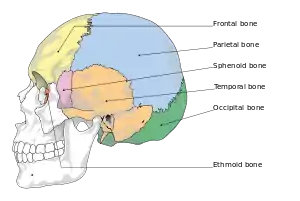

They typically require a significant degree of trauma to occur.[1] The break is of at least one of the following bones: temporal bone, occipital bone, sphenoid bone, frontal bone, or ethmoid bone.[1] They are divided into anterior fossa, middle fossa, and posterior fossa fractures.[1] Facial fractures often also occur.[1] Diagnosis is typically by CT scan.[1]

Basilar skull fractures include breaks in the posterior skull base or anterior skull base. The former involve the occipital bone, temporal bone, and portions of the sphenoid bone; the latter, superior portions of the sphenoid and ethmoid bones. The temporal bone fracture is encountered in 75% of all basilar skull fractures and may be longitudinal, transverse or mixed, depending on the course of the fracture line in relation to the longitudinal axis of the pyramid.[5]